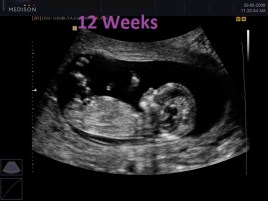

Fetology makes it undeniably evident that life begins at conception and thus requires all protection and safeguards that any of us enjoy. Why do the Repeal the 8th movement argue differently? Perhaps because if they argued with the truth they would have nothing to stand for. Instead they stand for a fully developed woman’s right to her body over that of the human life in the womb.

A pre-born baby is made up of human sperm and human ovum which can only lead to the creation of a human being. It is a naive argument to describe the unborn baby as just a clump of cells or simply a foetus (as if this takes away from its humanity). Those ‘clumps of cells’ are how every human being began, even the Repeal the 8th activists  who argue that abortion is not destroying human life. For some reason, just because the unborn begin as small cells means that they are not human or worthy of further development.

So how is it that the Repeal the 8th movement still believe that a clump of cells is not a human and deserves no chance at development? Is it because they are so small and do not look like born human beings?

It’s true that humans start out as those tiny cells, but “in the objective scientific sense she is every bit as human as any older child or adult. In fact, she looks just like a human being ought to look at her stage of development.5